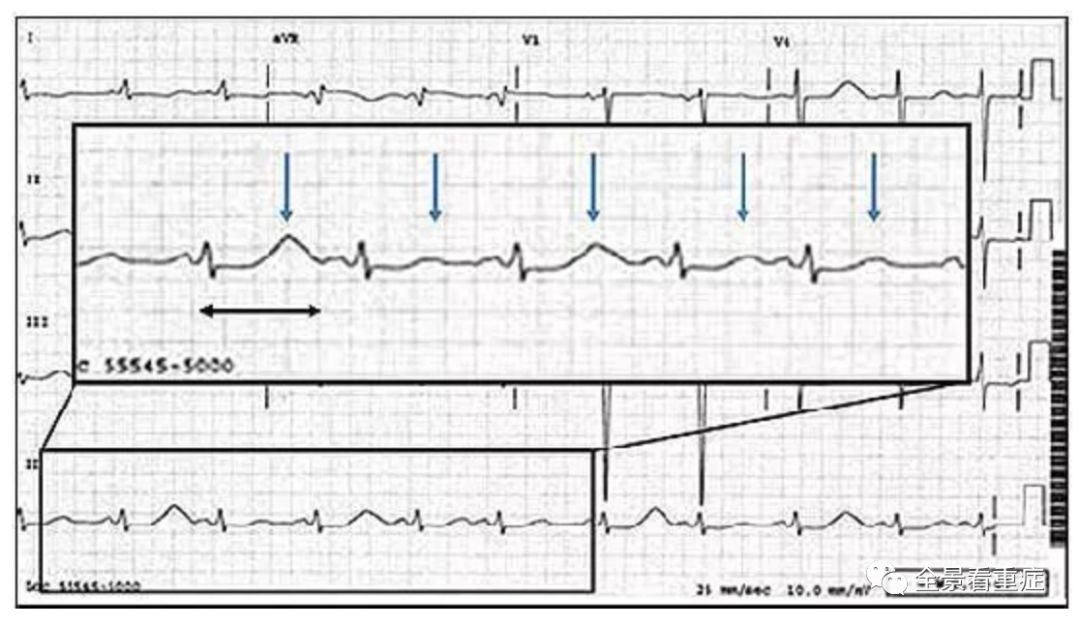

下图所示60次/分的窦性心律,QT间期(黑色双箭头)长至680ms,T波的高度呈交替变化(蓝色箭头),这样的变化往往是更严重的室性心律失常的前兆,如若不及时处理,可能会造成更为严重的后果。